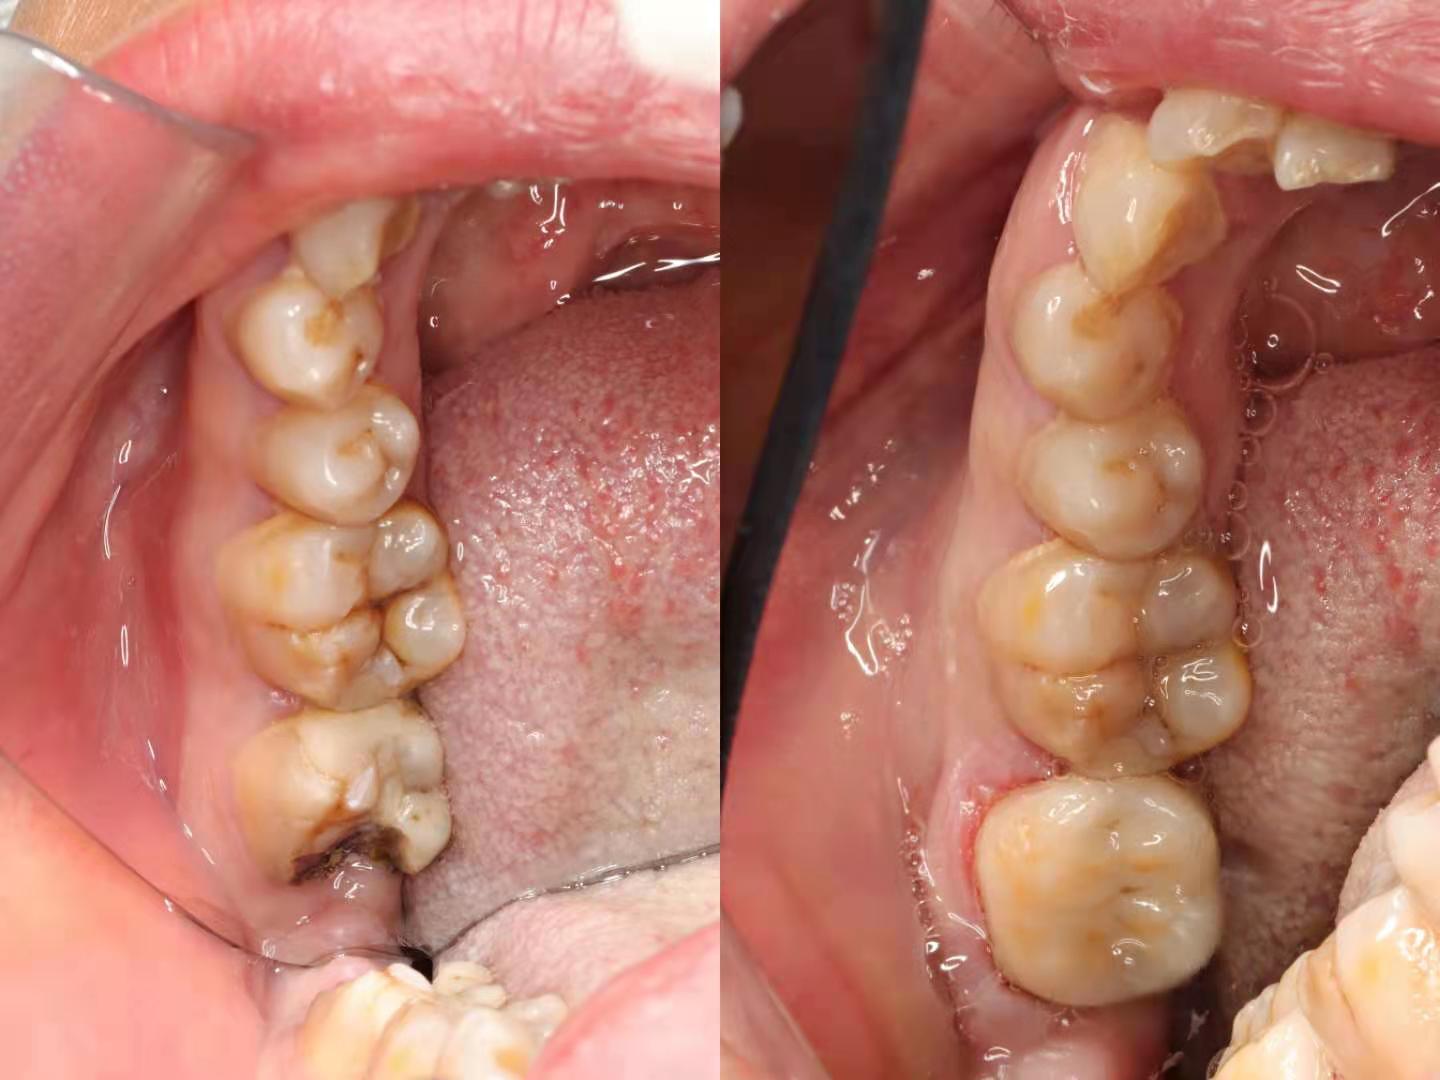

术前术后对比

针对相对大的牙体面积缺损、龋坏及多次充填治疗失败的患牙,利用数字化技术,CAD光学扫描得到精准数字模型,通过CAM技术打印出高精度修复体,利用橡皮章隔离技术确保了高强度的粘接,瓷嵌体修复远期治疗效果得到了保障。

与传统治疗方式相比,椅旁CAD/CAM技术不仅缩短了患者的就诊时间,减少了患者的就诊次数,同时也减少了多次复诊时对患牙的刺激,大大提高了治疗的效率以及成功率。实现了一次就诊当天戴牙的可能。